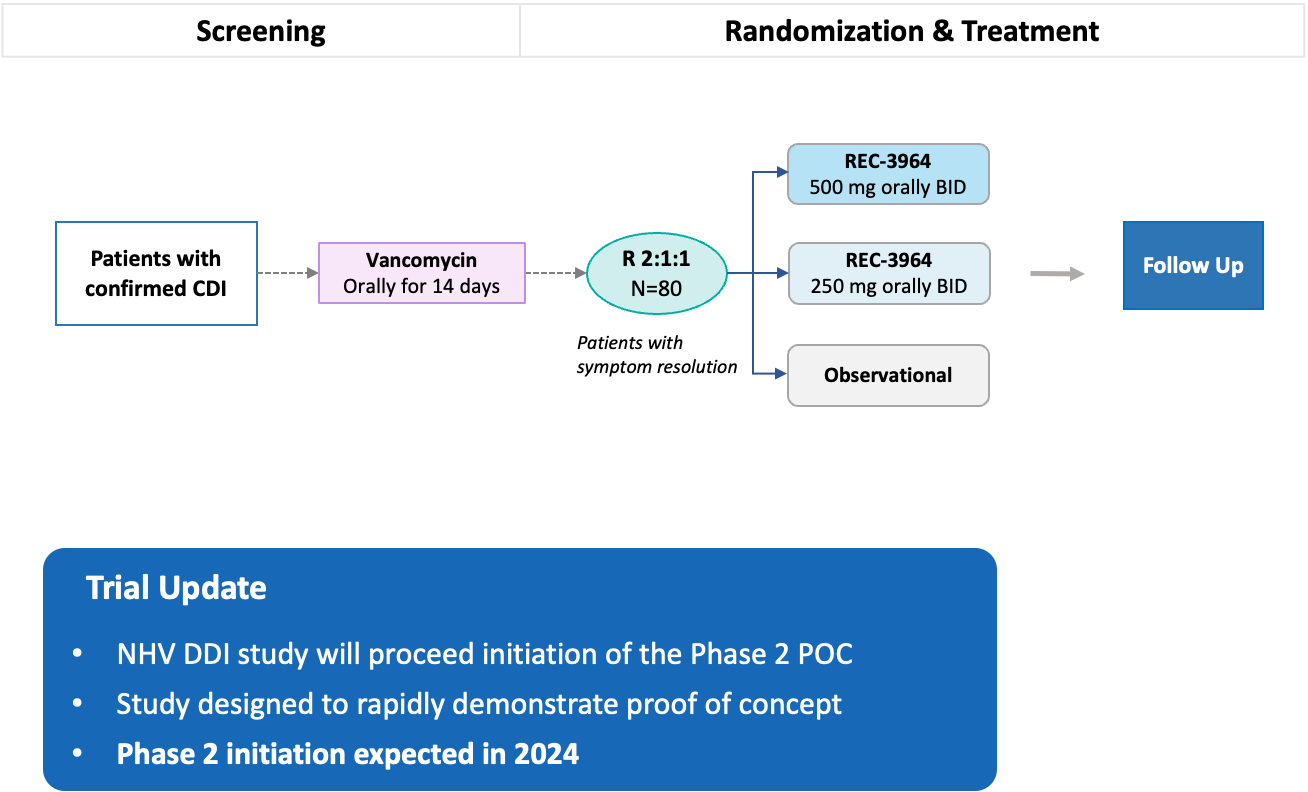

•Completed a Phase 1 study for REC-3964 in healthy volunteers for the potential treatment of Clostridioides difficile (C. difficile) infection with a favorable safety and tolerability profile